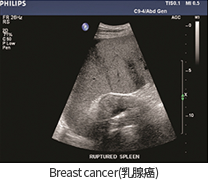

• Breast cancer(유방암)